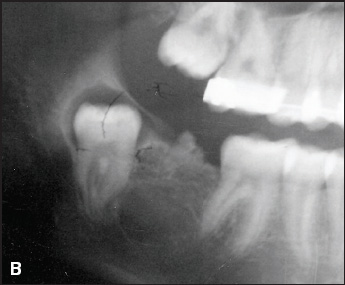

A progress panorex then displayed what appeared to be an odontoma (B), which was confirmed by biopsy. The x-ray also showed that the mandibular right second molar had fully formed, but had drifted so far distally that it had begun erupting superiorly into the ascending ramus. The crown of the tooth was surrounded by what appeared to be a dentigerous cyst.

The surgeon determined that the best course of action was to remove the wayward second molar, the surrounding cyst, and the odontoma. All went well, and healing was rapid and uneventful.